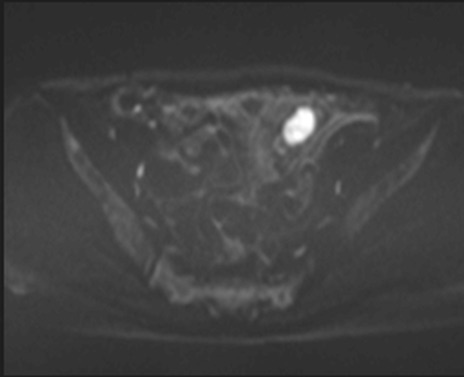

MRI(4日後)